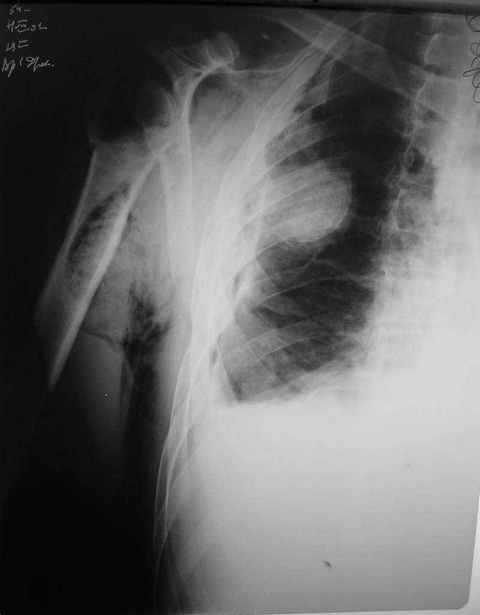

Уважаемые коллеги. Недавно из нашего отделения был выписан пациент 54 лет с закрытым переломом плечевой кости. Из анамнеза: за 2 дня до поступления в НИИСП, в состоянии алкогольного опьянения упал с лестницы на даче (высота 3-4 метра) с упором на правую руку. Через двое суток обратился за медицинской помощью. Доставлен бригадой "Скорой помощи".Правый плечевой сустав умеренно деформирован. По внутренней поверхности плеча имеется кровоподтек. При пальпации плечевого сустава имеется умеренная болезненность. Активные и пассивные движения болезненные. Снижена чувствительность по тыльной поверхности пальцев кисти и отсутствует активное разгибание кисти и пальцев. Имеется подкожная эмфизема шеи, верхней половины грудной клетки (рис 1, 2). На рентгенограмме: оскольчатый перелом головки плечевой кости со значительным смещением, перелом 2-3 ребер справа, тканевая эмфизема (рис 3). КТ при поступлении: перелом головки плечевой кости в области анатомической шейки со смещением отломка головки в грудную полость, правосторонний гидроторакс, перелом 2-3-4 ребер справа. (рис 4). Через двое суток после поступления выполнена операция: атипичная торакотомия, эвакуация свернувшегося гемоторакса, удаление инородного тела (головки плечевой кости) из плевральной полости (при этом выявлено имеющееся повреждение париетального и висцерального листков плевры) (рис. 5), дренирование плевральной полости, замещение проксимального конца плечевой кости спейсером из костного цемента с антибиотиком (рис. 6). Послеоперационный период протекал гладко. При контрольной рентгенографии положение спейсера удовлетворительное (рис. 7, 8). Дренаж из плевральной полости удален через 3 суток после вмешательства. Послеоперационная рана зажила первичным натяжением. Через 12 дней после операции больной выписан на амбулаторное лечение.